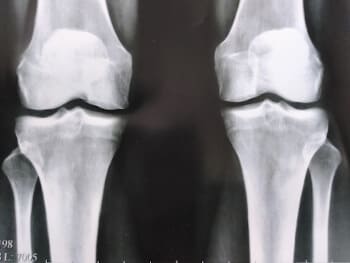

হাঁটু এন্ডোপ্রোস্টেসিস, ছবি